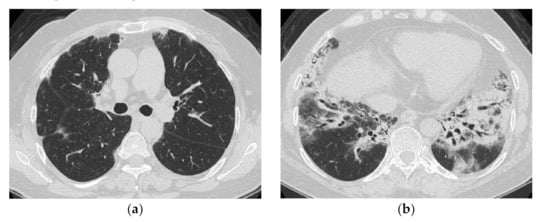

HRCT Findings of Patients with Anti-MDA5 Ab

| Distribution along the bronchovascular bundles in the bilateral lower lung fields > diffuse | Diffuse, predominantly in the lower lung fields, or both |

| Reduced volume of the lower lobes | Peribronchovascular lesion of the periphery of lower lobes, with parallel spread to the pleura |

| Reticular shadows or consolidation > GGO | Patchy distribution |

| Good response to treatment but relapses | GGO and consolidation |